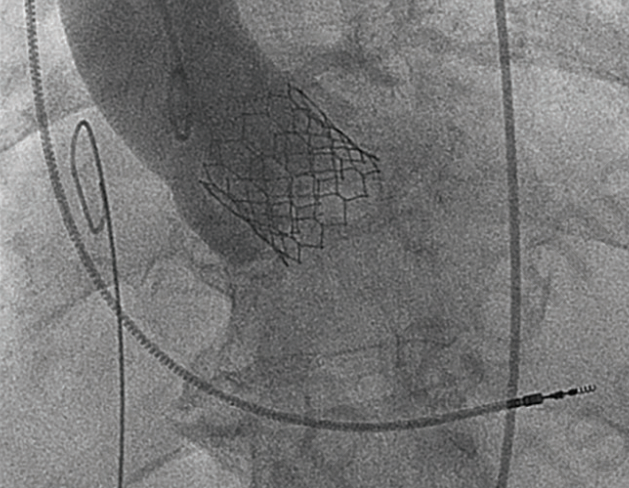

A long-sheath assisted transfemoral transcatheter aortic valve replacement (A-C: case 1; D-I: case 2). (A, B, D, E) Volume-rendering images of the aorta. (C) A successfully implanted valve. (F) Valve deployment. (G, H, I) Ascending aorta dissection (arrowheads) and dissection entry (arrows).

Reprinted with permission from Higuchi R, Nishida K, Saji M, Ohno M, Takamisawa I. J Invasive Cardiol. 2023 Apr;35(4):E221-E222.